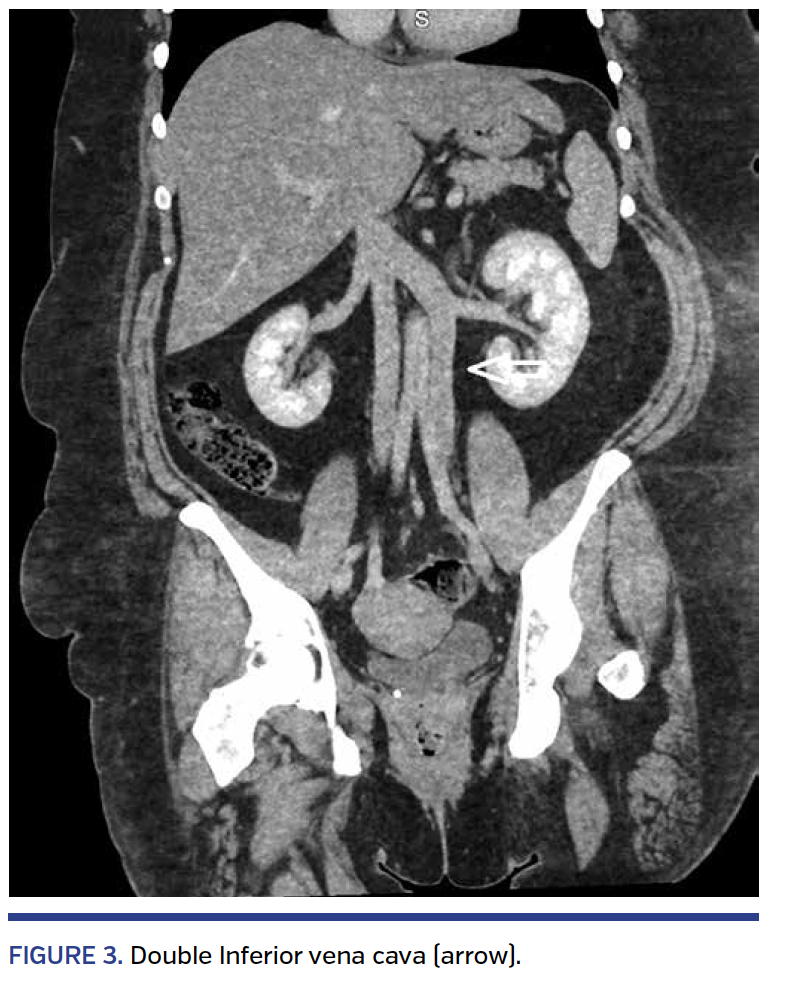

Anomalies of the IVC can be divided into four groups: prerenal, renal, postrenal, and multisegmental. The prerenal anomalies result from atresia or failure to unite the right subcardinal vein with the hepatic vein, leading to infrahepatic IVC interruption and drainage through the azygous vein. The renal anomalies are secondary to a persistent circumaortic venous ring (renal venous collar) or persistence of the dorsal limb but regression of the ventral limb of the circumaortic ring (retroaortic left renal vein) (Figure 2). The postrenal anomalies result from persistence of right and left supracardinal veins (double inferior vena cava [DIVC]) (Figure 3), persistence of left but regression of right supracardinal vein (left IVC), and persistence of right posterior cardinal vein (retroureteral IVC).2-5

Familiarity with anomalies of the IVC is of particular importance to the vascular or imaging specialist. In this manuscript, we discuss DIVC anomaly (present in 0.2%-3.0% of the population) and review its implications to diagnostic and interventional procedures. Diagnosis of DIVC is best made with multidetector computed tomography (CT) angiography or magnetic resonance imaging (MRI). Venography during the placement of IVC filters or during evaluation for venous compression syndromes (Figure 4) may identify this abnormality.

DIVC and vascular injury during retroperitoneal surgery. Knowledge of the presence of DIVC is important during abdominal and retroperitoneal surgery in order to avoid injuring the left IVC. Also, a duplicate IVC can be mistaken on CT of the abdomen with paraaortic lymphadenopathy. Furthermore, its presence can complicate surgery for aortic aneurysm. Finally, it is important for surgeons to evaluate whether a renal donor has DIVC to avoid injury to this vein and potential complications during harvesting of the kidney.6,7

Filter placement for patients with DIVC. In patients with DVT and requiring an IVC filter, it is important to determine whether DIVC is present. Venography should be considered in every patient with planned IVC filter placement to rule out this anomaly. If DIVC is present, a filter should be placed in both IVCs below the renal veins or a single IVC above the confluence of the left and right IVC (suprarenal segment). Failure to do so may result in failure to protect against a pulmonary embolus. Venography is also important to size the DIVC, as often they are of different sizes. Lack of visualization of the left iliac inflow and larger-than-expected left renal vein inflow are generally seen on venography.12-17

In summary, DIVC is likely to be encountered by the endovascular or surgical specialist. A high index of clinical suspicion is needed to uncover this anomaly. Evaluation by CT angiography or MRI is needed to identify its course and its relationship with the renal vein, its size when IVC filters are planned, the location of the left renal vein in relationship to the aorta, and for the planning of IVC filter placement in the setting of DVT and pulmonary embolism. Finally, this entity should not be mistaken for lymphadenopathy and its course should be well understood before abdominal and pelvic/retroperitoneal surgical interventions.